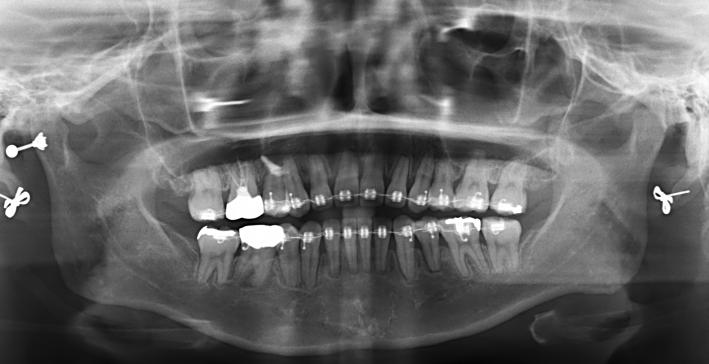

치료 막바지 입니다. 그런데 이게 교정이 잘되고 있는게 맞는건지 이제 장치 빼자 하면서 6개월이 흘렀고 이번 토요일에 빼자 하고 있습니다 아직 마음에 안드는게 많은데 엑스레이도 안찍어 보고 그냥 배열만 보고 ...